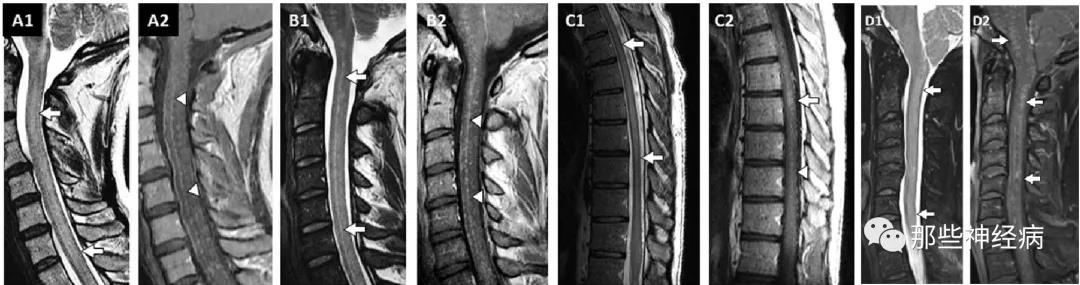

②脊髓受累MRI上常为长节段(>3个椎体节段)病灶,但显影相对模糊,不如AQP4抗体阳性和MOG抗体阳性的脊髓炎明显,边界不清,且少有脊髓肿胀。有时可见邻近脊髓中央管GFAP富集区的点状或线状强化病灶,也可有软脊膜强化。

(增强像见软脊膜和脊髓部分病灶线样强化)

泌尿功能障碍、勃起功能障碍、双足感觉障碍可能是脊髓圆锥损伤所致,在增强MRI上可见圆锥表面的软脊膜强化。

在这14例患者的影像学表现中,脊髓圆锥表面强化的比例高达71%!

在儿童脊髓病变中,同样可见脊髓圆锥表现软脊膜受累:

在中国人脊髓病变中,脊髓圆锥表面软脊膜受累常见:

在中国人脊髓病变中,颈髓表面软脊膜受累常见: